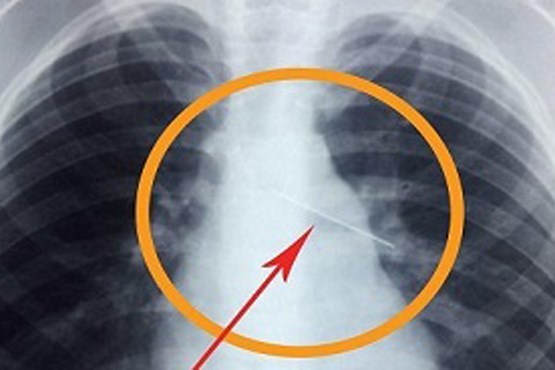

خارج کردن سوزن ۴ سانتی از کبد نوزاد ۱۱ ماهه

به گزارش میزان، تیم پزشکی بیمارستان پیامبر اعظم (ص) شهر قشم، سوزن 4 سانتی را از کبد و شکم کودکی 11 ماهه خارج کردند.